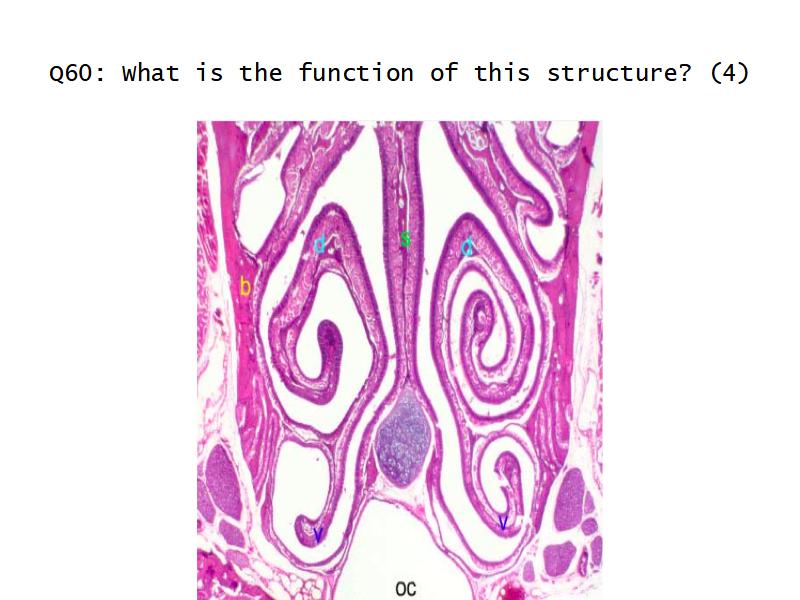

Function of the nasal cavity?

Function of the nasal cavity?

- Warm

- Moisture

- Filter

- Smell